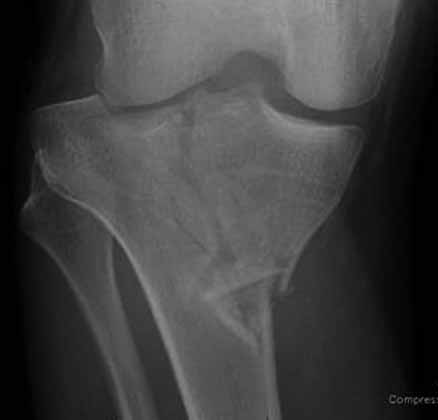

На снимке типичный перелом медиального тибиал плато с передним смещением (подвывих) по Schatzker IV. Консервативное лечение без медиальной опоры не может удержать деформирующие силы, и из-за вторичного смещения мыщелка конечность смещается в варус. Кроме передних смещений еще встречаются сложные фронтальные варианты переломов, и тогда голень подвывихивается кпереди.

А в данном случае мыщелок сросся со смещением кпереди и ротирован. За счет интактной наружной колонны опороспособность конечности сохранена, но остается варус и экстензия конечности. Для предоперационного расчета необходимо сделать на всю длину конечности рентгенограмму, а в остром периоде КТ и 3-мерный снимок помогут лучше ориентироваться в характере перелома.